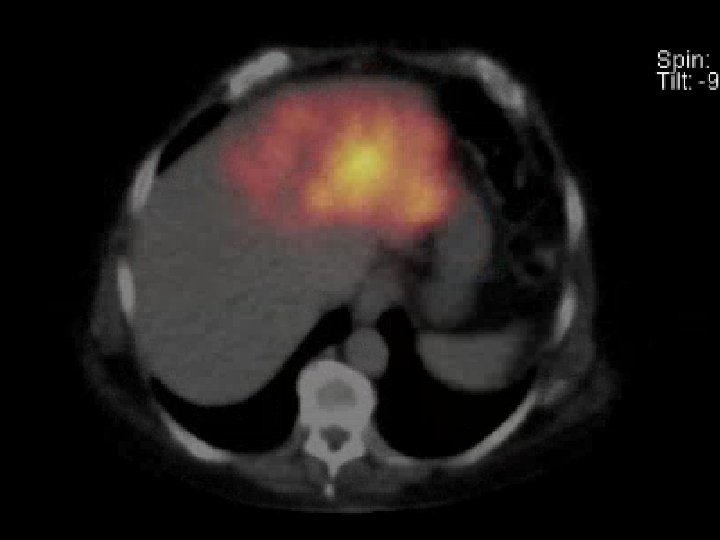

MAA Scan